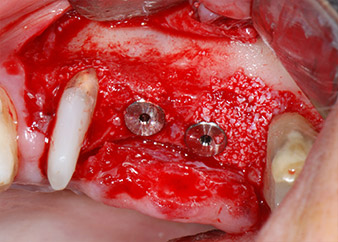

Dann wurden die Implantate (Restore, Keystone Dental) mit dem Implantatmotor eingesetzt (Abb. 11 und 12).

Schließlich wurde die Stelle nach einer Periostschlitzung mit resorbierbarem Nahtmaterial der Stärke 5/0 passiv mit einem koronalen Verschiebelappen vernäht (Abb. 15). Die postoperative Röntgenaufnahme zeigt beide Implantate in korrekter vertikaler Position (Abb. 16).